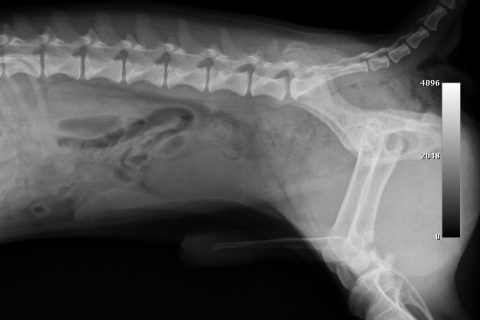

症例:大腿骨先端の骨折

今回は、大腿骨の先端が骨折した症状です。

専門的には、大腿骨遠位端骨折といいます。

この骨折は比較的珍しい骨折ですが、今回は滑車溝の真ん中で骨折した非常に珍しい骨折です。

大腿骨遠位端骨折は、比較的手術が難しい骨折です。当院では院内で矢状ピンを作成して手術しています。